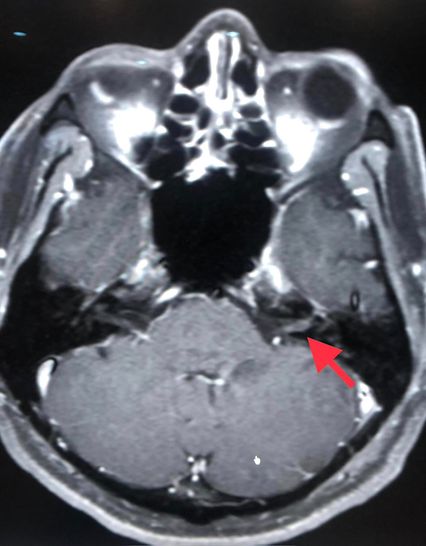

ผลการตรวจคลื่นแม่เหล็กไฟฟ้าสมอง (MRI brain) พบมีการอักเสบของเส้นประสาทในสมองข้างซ้ายเส้นที่ 7 และ 8 เจาะเลือดตรวจแอนติบอดีเฉพาะต่องูสวัด Varicella IgG >5,000 ให้ผลบวก Varicella IgM ให้ผลลบ และเมื่อเจาะหลัง ตรวจน้ำไขสันหลัง พบเม็ดเลือดขาวในน้ำไขสันหลังสูง 188 เชลล์ เป็นชนิดลิมโฟไซต์ (lymphocyte) 100% ค่าโปรตีนสูงเล็กน้อย 58.3 ค่าน้ำตาล ปกติ 76 ส่งตรวจรหัสพันธุกรรม PCR น้ำไขสันหลังพบเชื้อไวรัสงูสวัด (Varicella Zoster Virus )

แพทย์วินิจฉัยว่า ติดเชื้อไวรัสวาริเซลลา (Varicella Zoster Virus: VZV) ไวรัสงูสวัด ซึ่งเป็นไวรัสชนิดเดียวกันกับไวรัสโรคอีสุกอีใส มีอาการแทรกซ้อน เส้นประสาทในสมองข้างซ้ายเส้นที่ 7, 8, 9, 10 อักเสบ และเยื่อหุ้มสมองอักเสบ ให้ยาฆ่าเชื้อไวรัส acyclovir ทางเส้นเลือดนาน 14 วัน และให้ยาเสตียรอยด์ร่วมด้วย